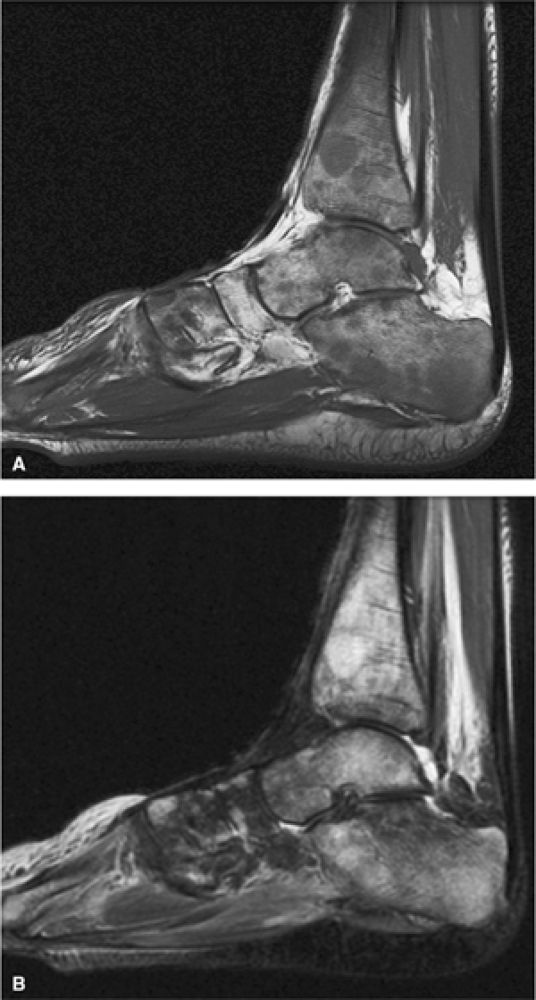

FIGURE 13.19 ● Diffuse marrow infiltration of the ankle in a patient with chronic myelogenous leukemia. Sagittal T1-weighted image (A) shows diffuse low-signal leukemic infiltration, which is bright on the corresponding sagittal STIR image (B).

In the acute phase of chronic leukemia, particularly in chronic myelogenous leukemia patients in blast crisis, there is almost complete replacement of both red and yellow marrow areas. The decreased signal on T1-weighted sequences represents replacement of marrow fat by tumor cells, which have a significantly longer T1 relaxation time. On STIR images, tumor cells appear as areas of white on a black or gray background (Fig. 13.19).